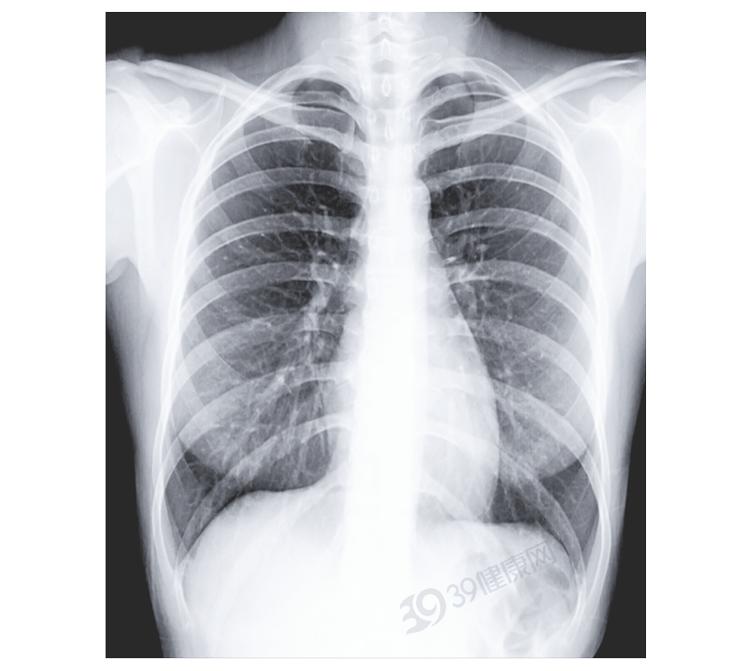

肺癌、肺气肿、肺炎、纵膈疾病等胸部问题;

就像把面团擀平,X光会穿透身体,遇到骨头等密度大的组织就被挡住,成像时这些地方会变成白色。

不过它有个缺点,这种平扫方式会把所有组织会重叠在一起,就像只拍了一张平面的照片,有时候需要换个角度再拍一张。

好在它的辐射量比较低,是CT的1/10~1/100,适用于初筛骨折、肺炎等。

如果说X光是一张照片,那CT就是把身体“切”成一层层薄片,能看到更多细节。

辐射量比X光高,但比想象中安全,适用于癌症筛查、肺部精细检查、脑出血等。